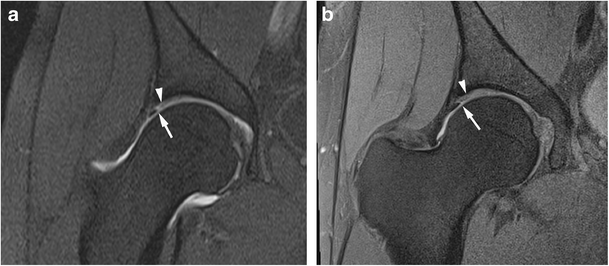

figure 4

Anterosuperior acetabular labrum complete tear with adjacent full thickness cartilage defect in a 26-year-old confirmed at surgery. Sagittal (a) T1 FS 1.5T MRA shows complete basal labral tear (arrow) and normal articular cartilage and (b) PD FS 3T MR image shows complete basal labral tear (arrow) and full thickness cartilage defect (arrowhead)

Anterosuperior partial thickness cartilage defect in a 32-year-old confirmed at surgery. Sagittal (a) T1 FS 1.5T MRA shows normal articular cartilage at the junction with the labrum (arrowhead) and (b) PD FS 3T MR image shows partial thickness cartilage defect (arrow)